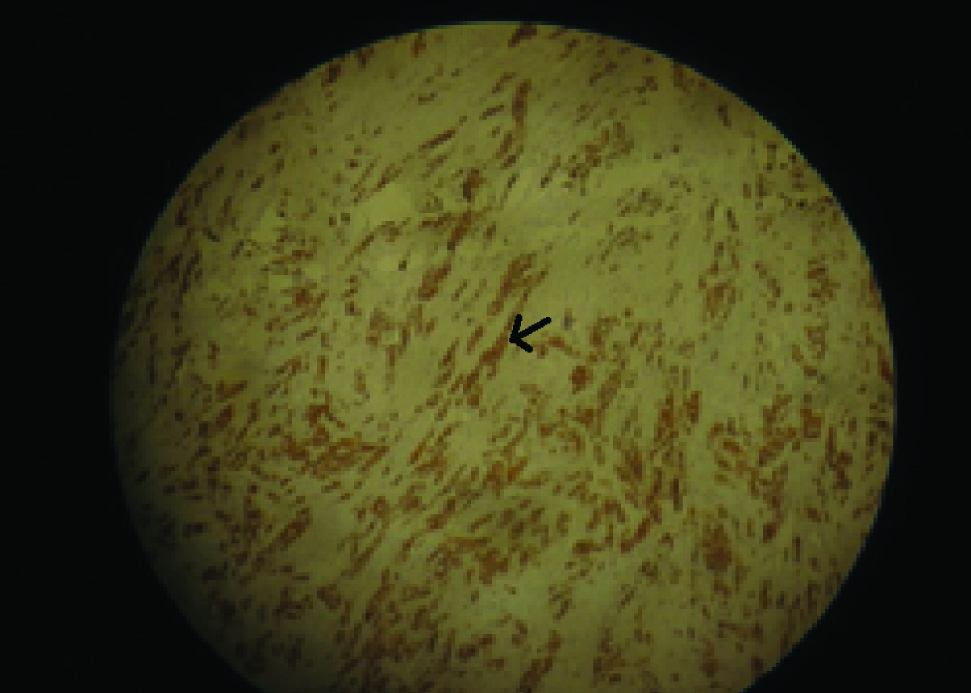

Microscopy showed tumour cells which are predominantly having spindle cell morphology [Table/Fig-6] and occasional epitheloid cell, arranged in interlacing bundles of varying length. There was evidence of cellular pleomorphism with large vesicular nuclei and few mitotic figures. Some area of focal necrosis and haemorrhage was seen. There was also evidence of dense fibrous connective tissue stroma with minimal vascularity. Immunohistochemically the tumour cells were positive for Cytokeratin [Table/Fig-7] and S-100 [Table/Fig-8]. Vimentin [Table/Fig-9] was positive in the connective tissue stroma. Smooth muscle actin (SMA) [Table/Fig-10]showed focal positivity in the connective tissue around the blood vessels and Desmin [Table/Fig-11] was negative.

Cyotokeratin positive under 10x magnification